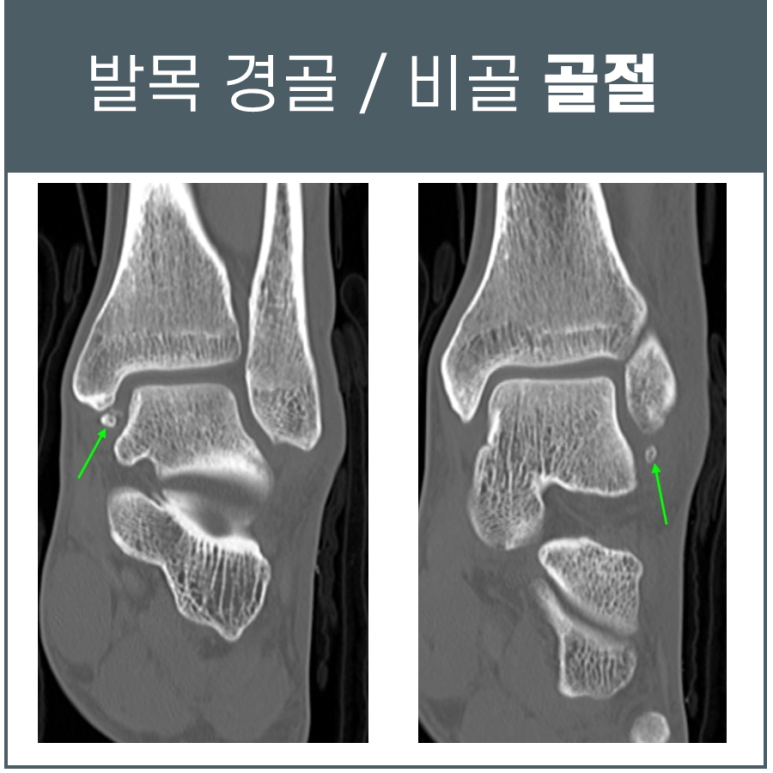

일단 예전에 다치셨던 복숭아뼈 안쪽과 바깥쪽 2곳에 오래된 골절이 확인되었습니다.

이런 경우는 과거에 인대가 늘어나면서 붙어있던 뼈를 잡아당겨 발생한 견열골절(avulsion fracture)이 있었던 건데요.

이미 멀리 떨어져나간 작은 뼈 조각(bone fragment)이 원래 부위로 아물지 않고 남아있는 환자분들이 굉장히 많습니다.